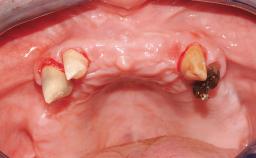

| Case Type | Single-Tooth Space |

|---|---|

| Jaw | Maxilla |

| Area | Posterior |

| # of Teeth | - |

| # of Implants | - |

| Type of Implants | - |

| Attachment | - |

| Bone Augmentation | - |

| Augmentation Materials | - |

| Guided Surgery | - |

| Soft Tissue Grafting | - |

| Abutment Type | - |

| Prosthesis Type | - |